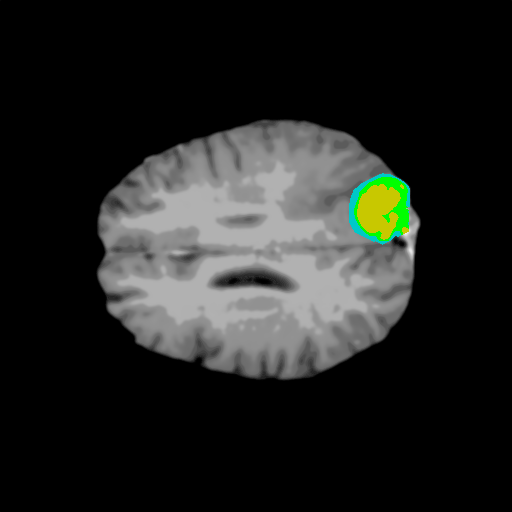

Extensive experiments have been performed in the current setup, and experimental outcomes are reported with the demonstration of numerical and statistical analyses using the proposed QFS-Net, QIS-Net [39], convolutional U-Net [18] and Residual U-Net (URes-Net) architectures [20]. The human expert segmented skull-tripped contrast enhanced DSC brain MR input image slices of size and ROIs are provided in Figure 5 as samples. The demonstration of QFS-Net segmented images followed by the essential post-processed outcome on the slice no. for class level with four distinct activation schemes () are shown in Figure 6. It is evident from the experimental data provided in Table LABEL:tab1 that the proposed QFS-Net performs optimally for the -connected quantum fuzzy pixel information heterogeneity assisted activation () with and gray scale set in comparison with other thresholding schemes and gray scale sets under the four evaluation parameters () [44]. The segmented tumors obtained using the proposed self-supervised procedure under class transition levels with four different thresholding schemes , , and are demonstrated in Figures 7- 8 for the class boundary sets and [39], respectively. The segmented images using the remaining two class boundary sets ( and ) [39] are provided in the supplementary materials section. The segmented ROIs describing the whole tumor region after the masking procedure using QIS-Net, U-Net and URes-Net are also reported in Figure 9.